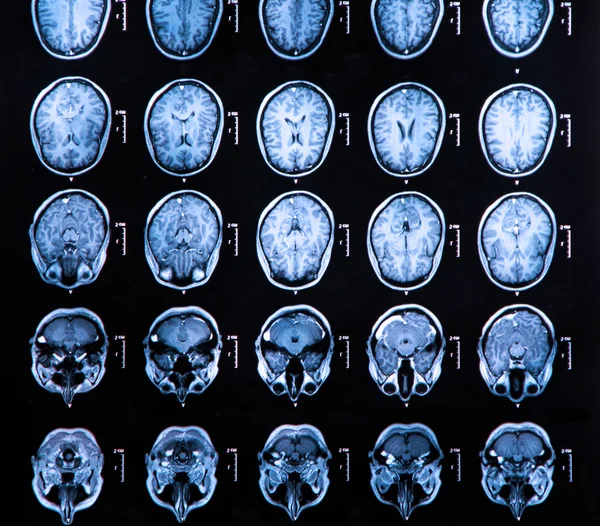

Engineer Team : RESONANCIA MAGNETICA Magnetic Resonance Imaging – Clinical Images Hallazgos por resonancia magnética cerebral de nuestro paciente. M, 21 … Imágenes por resonancia magnética anormales como predictoras de mal … Imágenes por resonancia magnética anormales como predictoras de mal … Lesiones en resonancia magnética (RM) del encéfalo y la médula espinal … Pin en Resonancia Magnética del Encéfalo A) Resonancia magnética cerebral (RMC) mostrando infartos en … Caso 1: Edema cerebral visualizado mediante RM. (A) Secuencia T1 plano … Rascacielos dormir pasta tac y resonancia diferencias retrasar … Pin on Apuntes de Enfermería y T.C.A.E Resonancia magnética cerebral secuencia T2, que muestra lesión … Meningitis aguda en la enfermedad de Behçet | Reumatología Clínica Resonancia magnética coronal normal del cerebro Fotografía de stock – Alamy Imágenes de resonancia magnética, la imagen de la cabeza en diferentes … Resonancia magnética cerebral A) protocolo T1 sagital (Caso 1). Se … Resonancia magnética cerebral. Secuencia T1 corte sagital. Atrofia … Resonancia magnética de cerebro, cortes axiales, secuencias T2. Señal … Resonancia magnética de cráneo. A y B) Cortes axiales FLAIR … Resonancia magnética (RM) de cerebro, corte axial ponderado en T2: la … RM cerebral: Interpretación paso a paso | Kenhub Resonancia magnética de cerebro, cortes axiales, secuencias T2. Señal … De Resonancia Magnética De Cerebro Foto de archivo – Imagen de arteria … Top 107+ Imagenes de resonancia cerebral normal – Destinomexico.mx -Imagen por resonancia magnética del cerebro. a) Cortes sagital y axial … resonanCia magnétiCa Cerebral donde se observa hiperintensidad a nivel … MRI (Imagen de resonancia magnética) – Tomografía computarizada de la … Meningioma – NCI Imágenes por resonancia magnética coloreadas del cerebro sano del … Resonancia magnética cerebral en secuencia FLAIR, que muestra lesiones … Contraste resonancia magnetica cerebral – senturinthegreen Relación de los espacios de Virchow-Robin con la enfermedad de … Gliomatosis cerebral – Instituto Nacional del Cáncer Pin en Neurology. Recomendaciones para la utilización e interpretación de los estudios de … Fotografía De La Proyección De Imagen De Resonancia Magnética Del … atmósfera Dirigir Cumplir anatomia resonancia magnetica Desarrollar … Pin en #MEDICINA,#SALUD Resonancia magnética de la nasofaringe De Resonancia Magnética De Cerebro Foto de archivo – Imagen de polilla … Atrofia cortical global de predominio parietal en la Resonancia … Resonancia magnética cerebral | Download Scientific Diagram Neuroblog: Resonancia magnética cerebral en la trombosis crónica de … De Resonancia Magnética De Cerebro Imagen de archivo – Imagen de … ¿Cuáles son los riesgos de la resonancia magnética? – Integra Salud … Resonancia magnética cerebral al decimocuarto día de ingreso: área … Resonancia magnética. Corte axial mostrando área infartada en el … Resonancia magnética cerebral del paciente AV evidenciando lesiones en … -Ressonância magnética de encéfalo mostrando múltiplas imagens … Resonancia magnética cerebral secuencia FLAIR (Fluid Attenuated … Resonancia magnética cerebral con protocolo de epilepsia, en sección … Resonancia magnética cerebral en corte sagital. Se observa una evidente … Resonancia magnética craneal en la que se evidencian lesiones … Logran visualizar el cerebro a detalle más completo tras una resonancia … Así decide el cerebro la severidad de un castigo De Resonancia Magnética De Cerebro, Imagen de archivo – Imagen de … A) Resonancia magnética cerebral; Secuencia Tof: oclusión de arteria … Un estudio asocia la ansiedad con la aparición rápida del Alzheimer IMÁGENES DE 18 F-PR04.MZ PET FUSIONADA CON RESONANCIA MAGNÉTICA … Imágenes por resonancia magnética anormales como predictoras de mal … Tumores de la región pineal – Instituto Nacional del Cáncer Epilepsia: una historia de voces y fantasmas | Neurología Contribución de las imágenes de resonancia magnética por tensor de … Resonancia magnética secuencia T2 plano coronal de quiste epidermoide … Resonancia Magnética Cerebral del paciente: a. Aumento de… | Download … Resonancia magnética cerebral 2022 Síndrome de hemiconvulsión-hemiplejía-epilepsia. Seguimiento de un caso … Enfoque Radiologico: La resonancia magnética permite detectar lesiones … Resonancia magnética craneal T1 con contraste que muestra angiomatosis … guidewiz – Blog Resonancia magnética cerebral, secuencia SWI. Ribete hipointenso en la … resonAnCiA mAgnétiCA de ColumnA Con gAdolinio. Corte sAgitAl en t1 de … SEMANA 12: FUNDAMENTOS DE RESONANCIA MAGNÉTICA NUCLEAR. INDICACIONES Y … DIAGNÓSTICO DE ESCLEROSIS MÚLTIP Magnetic resonance imaging of the brain – Alchetron, the free social … Resonancia magnética de órbitas | Instituto Radiológico Dr. E Castillo Alteración de la marcha en un paciente post-trasplante hepático Resonancia magnética cerebral de un paciente sano (Ay B) y paciente que … Utilidad de la resonancia magnética craneal para el diagnóstico de la … Resonancia Magnética Del Cerebro El Tumor Cerebral Foto de stock y más … De Resonancia Magnética De Cerebro Imagen de archivo – Imagen de … ABDALLA RADIOLOGIA: NEURINOMA ACUSTICO Atrofia cortical global de predominio parietal en la Resonancia … Resonancia Magnética : Producción de la imagen MRI Brain Scan — Stock Photo © Bunyos30 #18724051 Mri (imagen de resonancia magnética) Monitor con imagen de captura de … Tomografía computarizada vs resonancia magnética: diferencia y … Tumores Cerebrales – Unidad de Neurocirugía RGS Resonancia magnética de la columna, sección sagital. Observe los discos … La resonancia magnética, una técnica imprescindible en el diagnóstico … Perfusión Cerebral por Resonancia Magnética | ¿Qué es? ¿Necesita Contraste? Resonancia Magnética Cerebro A: resonancia magnética, T2 coronal preoperatoria; se observa lesión en … Resonancia magnética cerebral — Foto de stock © Bunyos30 #27340623 La resonancia magnética se perfila como detector de mentiras | Futuro … Resonancia magnética cerebral en T1 con gadolinio, cortes axial (a … MRI brain : show brain tumor at right parietal lobe of cerebrum — Stock … NEUROIMÁGENES EN ENFERMEDAD DE PARKINSON: ROL DE LA RESONANCIA …